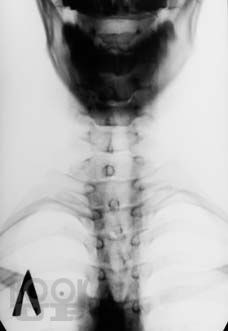

Рентгенодиагностика дегенеративно-дистрофических изменений позвоночника

В пособии отражены современные данные о рентгенологической диагностике дегенеративно-дистрофических заболеваниях позвоночника с учетом позиций мануальных терапевтов.

Пособие предназначено для мануальных терапевтов, вертебрологов, остеопатов, неврологов, студентов и преподавателей вузов медицинских и биологических специальностей. Пособие соответствует программе профессиональной переподготовки мануальных терапевтов и содержит 23 рисунка, 16 таблиц и тестовые задания.